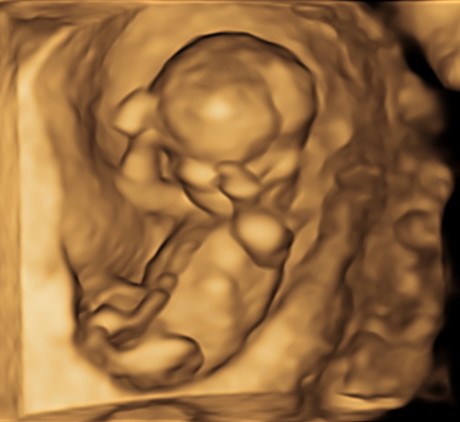

Indipendentemente dalla nostra scelta, è di capitale importanza fare comunque una ecografia fra la 11° e la 13° settimana. Infatti già a questa epoca gestazionale siamo in grado di condurre un’iniziale valutazione morfologica. Ma soprattutto questo è la finestra di opportunità per studiare la translucenza nucale. In realtà questa ampia finestra di tre settimane ha il suo momento più favorevole a 11 settimane e mezza e inizio dodicesima.

Si va a misurare quindi attraverso una ecografia lo spazio dietro la nuca: è una fisiologica raccolta di linfa che tende ad aumentare in diverse situazioni patologiche risultando essere un indice generale di buon andamento della gravidanza dove più è sottile più siamo tranquilli a riguardo di patologie cromosomiche, malformazioni cardiache, ed alcune malattie genetiche.

In questi 4/5 centimetri la risoluzione degli apparecchi moderni riesce a fare una prima valutazione morfologica, per vedere che ci siano tutti i “necessori” ed eventualmente anche accessori: cercando è possibile evidenziare il tubercolo genitale (sempre che il piccolo decida di essere collaborante e mostrare le proprie grazie). Si chiama così perché clitoride e pisellino hanno le stesse dimensioni a questa epoca, ma è possibile riconoscerli in base all’angolo rispetto al corpo: parallelo al corpo per le signorine, verso l’alto per i maschietti. Attenzione però la sensibilità, ovvero quanto ci azzecchiamo, è intorno al 60%.

La parte morfologica è molto importante, riusciamo a studiare l’estremo cefalico – a questa epoca il cervello fetale è molto semplice – , il massiccio facciale con occhi, naso bocca, le orecchie sono abbastanza facili da essere evidenziate. Nel torace oltre ai campi polmonari possiamo vedere il cuore battere ritmicamente e confermare la presenza delle quattro camere cardiache. Nell’addome riusciamo ad evidenziare lo stomaco e l’inserzione del cordone ombelicale. Si nota la presenza della vescica e del tubercolo genitale. Si possono esplorare tutti e quattro gli arti.

Per i genitori vedere sotto i propri occhi prendere forma il tesorino risulta una esperienza indimenticabile e impareggiabile al limite fra incredulità e la sorpresa come tutto sia già presente seppur in scala ridotta.